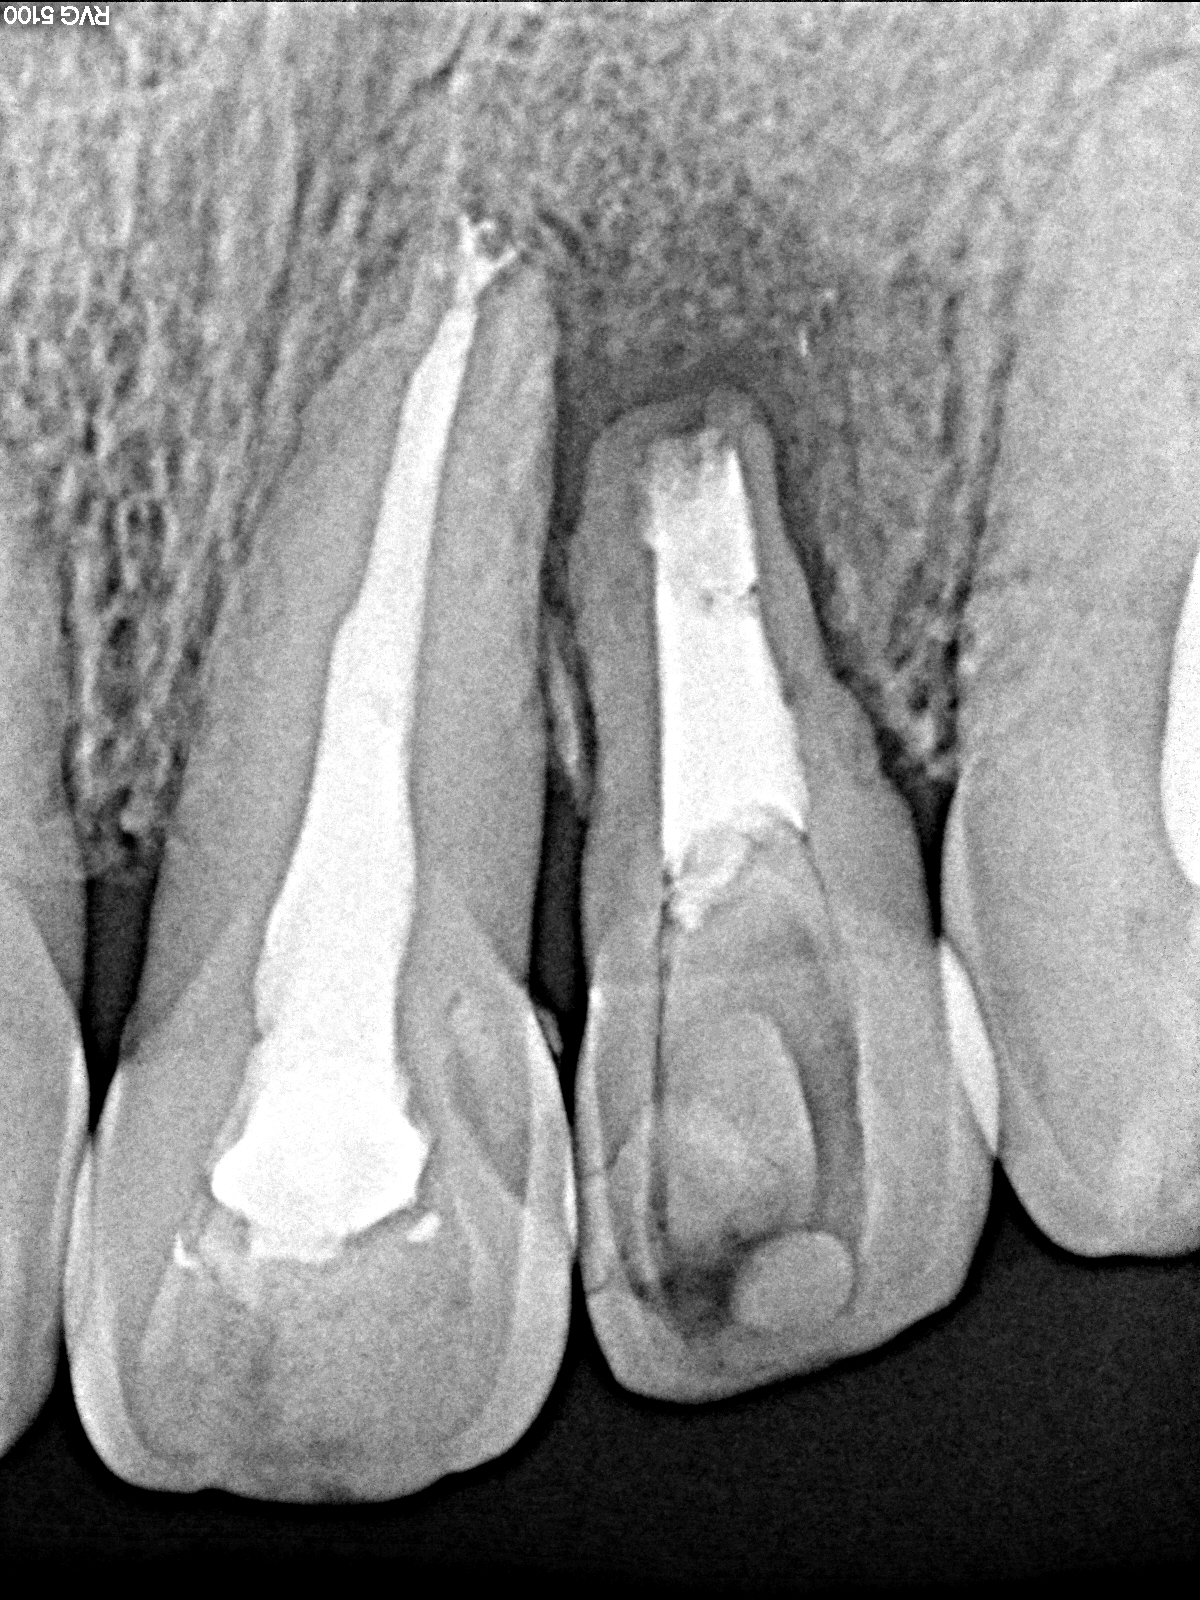

左上2番 根端切除しても治らなく来院 抜歯後ブリッジへ|お知らせ |広島市安佐南区の歯科医院 左上2番 根端切除しても治らなく来院 抜歯後ブリッジへ トップ お知らせ・ブログ お知らせ 左上2番 根端切除しても治らなく来院 抜歯後ブリッジへ 左上2番 根端切除しても治らなく来院 抜歯後ブリッジへ 正面観 問題の歯になります 咬合です 根尖病巣となっていました 抜歯させてもらいましたが、真っ黒です 補填材を入れて縫合して仮歯を入れて終了です ひどく歯茎の下がりも凹みも最小限で済んでいるかと思います 最終補綴は保険のブリッジを入れています Web診療予約 初めての方へ 選ばれ続ける理由 院内設備について 歯が痛いしみる一般歯科 歯がぐらぐらする歯周病 健康な歯を保ちたい予防歯科 子供の虫歯予防をしたい小児歯科 銀歯をセラミックに審美歯科 白い歯を目指しませんか?ホワイトニング 矯正専門医がいるので安心矯正歯科 抜けた歯を補いたいインプラント・入れ歯 医院案内 スタッフ紹介 メリィハウス歯科クリニックオフィシャルホームページ ラベンダー歯科クリニックオフィシャルホームページ お知らせ・ブログ ホーム 診療科目 一般歯科 歯周病治療 予防治療 小児歯科 審美治療 ホワイトニング 矯正歯科 入れ歯・インプラント マウスピース矯正 初めての方へ 院長・スタッフ 設備紹介 医院案内・アクセス メニューを閉じる